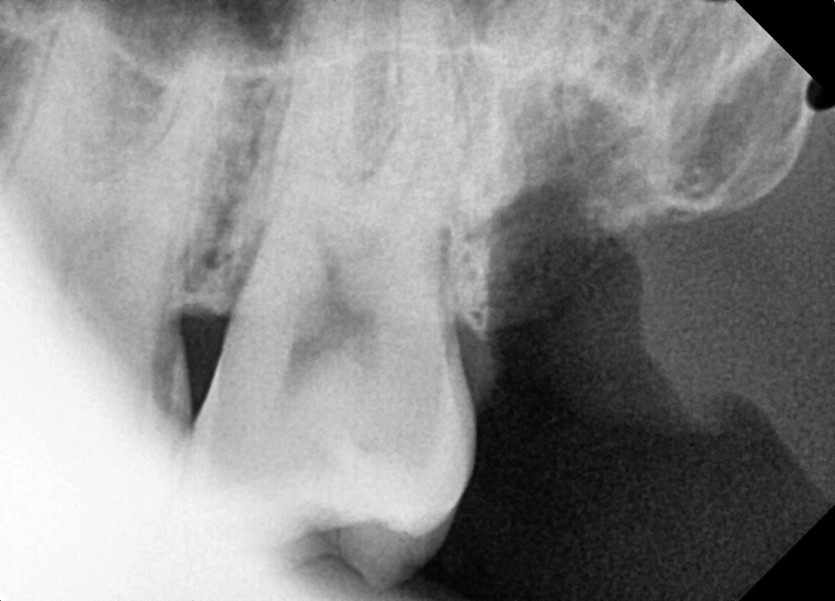

#28,38 사랑니 발치

구강 외과 전문의가 당일 발치했습니다.